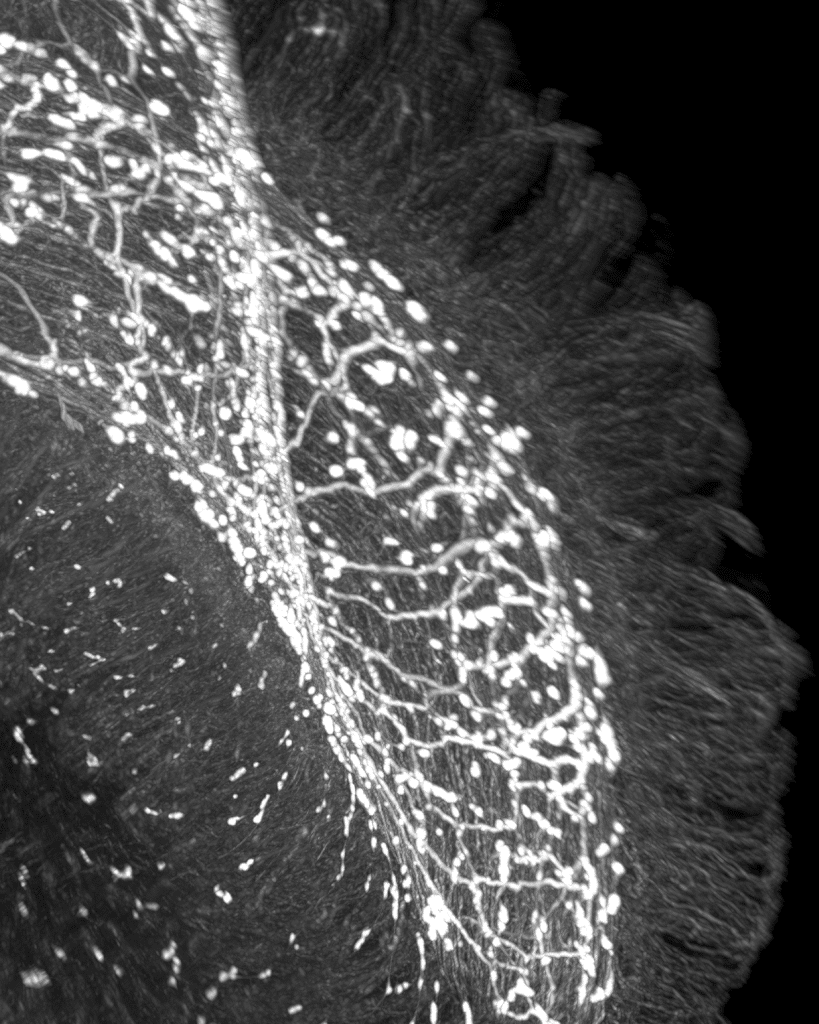

Cientistas da Fundação Champalimaud descobriram em experiências com ratinhos que o sistema nervoso do intestino atua como ‘agulhas em carris’, decidindo “qual o percurso que o sistema imunitário deve seguir”, se atacar bactérias ou tumores ou reparar tecidos.

“Quando o ‘carril de ataque’ está ativo, as células imunitárias percorrem o revestimento intestinal e eliminam bactérias e células tumorais. Quando o ‘carril de reparação’ é acionado, o mesmo tecido concentra-se na regeneração, reconstruindo a delicada barreira epitelial que mantém os microrganismos nocivos no exterior”, sintetiza, em comunicado divulgado ontem, pela Lusa, a Fundação Champalimaud.

Nas experiências feitas com ratinhos, Henrique Veiga-Fernandes e restante equipa verificaram que quando ativaram os neurónios (células do sistema nervoso) no intestino que libertam o neurotransmissor VIP as células epiteliais começaram a produzir citocinas (proteínas) que estimularam a resposta imunitária em modo de ataque do organismo, utilizado para destruir bactérias, células infetadas ou tumorais.

Segundo os cientistas da Fundação Champalimaud, as citocinas acabam por funcionar como a linguagem que as células epiteliais usam para comunicar com as células imunitárias.

“Diferentes células imunitárias possuem diferentes recetores para estas citocinas, por isso, dependendo de quais são libertadas, o sistema imunitário sabe se deve atacar ou reparar”, assinala Roksana Pirzgalska, primeira autora do estudo, citada no mesmo comunicado.